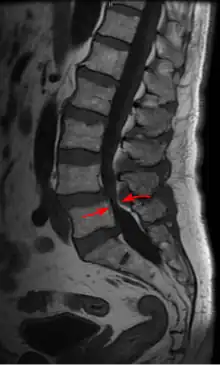

| Lumbar vertebra showing central stenosis and lateral recess stenosis. | |

Spinal stenosis may be congenital (rarely) or acquired (degenerative), overlapping changes normally seen in the aging spine.[6][7] Stenosis can occur as either central stenosis (the narrowing of the entire canal) or foraminal stenosis (the narrowing of the foramen through which the nerve root exits the spinal canal). Severe narrowing of the lateral portion of the canal is called lateral recess stenosis. The ligamentum flavum (yellow ligament), an important structural component intimately adjacent to the posterior portion of the dural sac (nerve sac) can become thickened and cause stenosis. The articular facets, also in the posterior portion of the bony spine can become thickened and enlarged, causing stenosis. These changes are often called "trophic changes" or "facet trophism" in radiology reports. As the canal becomes smaller, resembling a triangular shape, it is called a "trefoil" canal.